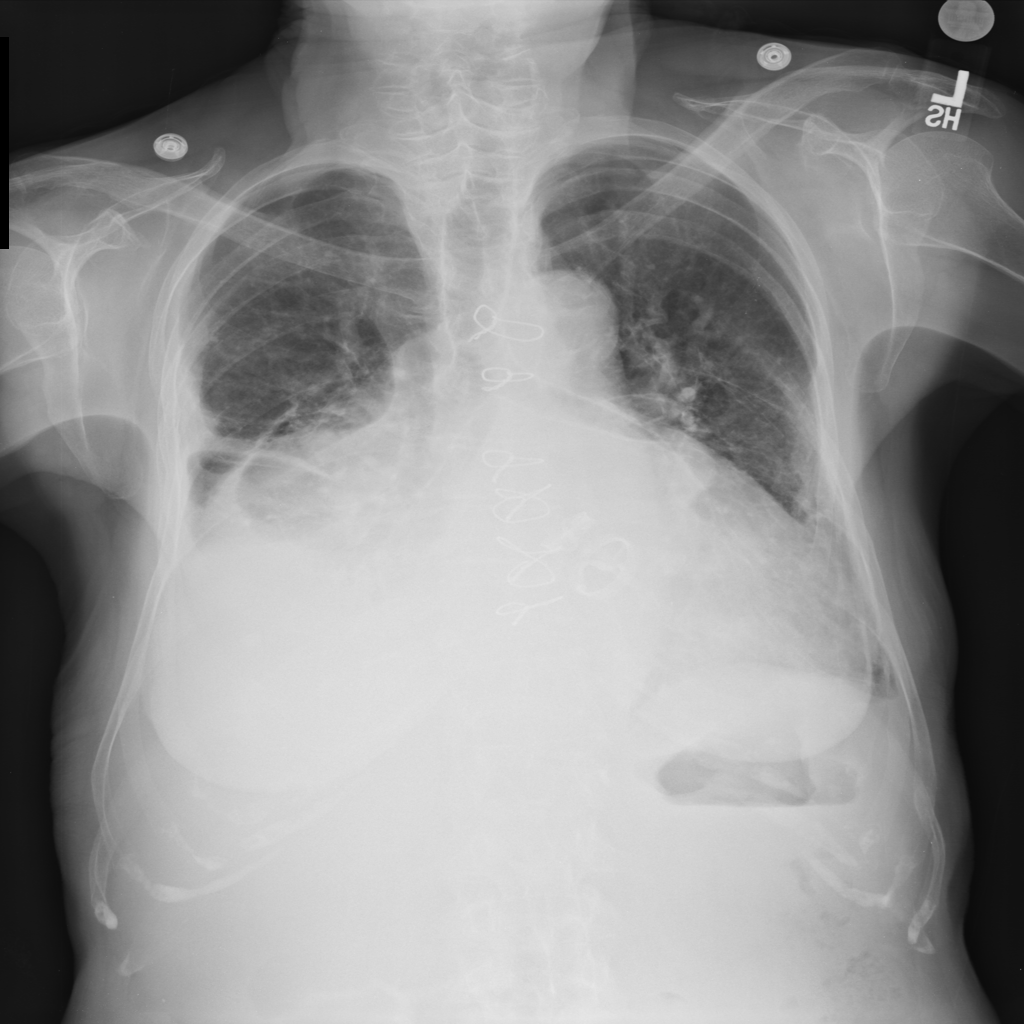

PAT-4639 · IMG-021Effusion

PAT-4639 · IMG-021

PA